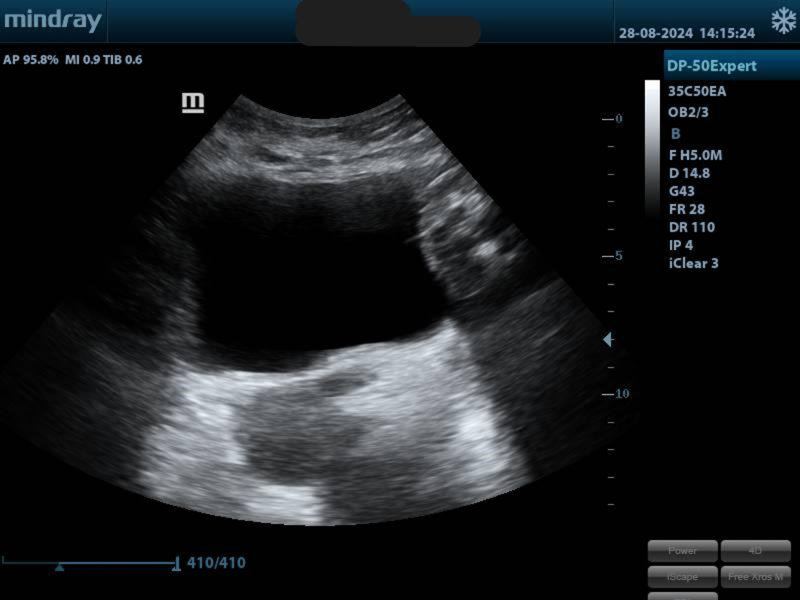

When placing the probe on the lower tummy, we can get an image of the bladder.

We will check if the shape and volume are normal. We will measure your bladder before and after urination, checking if any residue subsists. We can also assess its support when coughing, pushing and contracting the pelvic floor muscles.

Another way to check your pelvis area is with a trans-perineal view (the probe will be placed on your perineum). It will give us a picture of your internal organs:

You will be able to see where your organs are, what happens when you contract your pelvic floor, when you hold or relax it, when coughing, pushing, laughing, moving… and if there is any sign of prolapse.